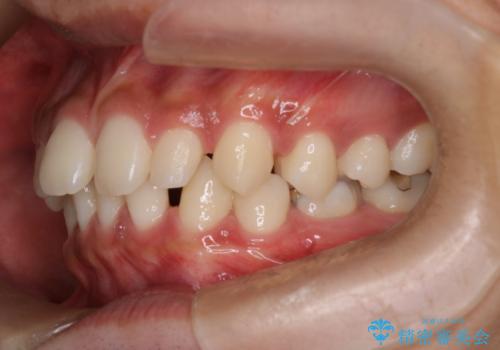

【インビザライン】空隙歯列の矯正

- 前歯の隙間を主訴に来院されました。

なるべく目立たない治療を希望されましたので、インビザラインにて治療を行なっております。

単純に前歯の隙間の閉鎖をしてしまうと、前歯に早期接触が生まれ、臼歯が噛まなくなってしまいます。適切な治療計画を立てることで、噛み合わせも良好な結果を得ることができました。